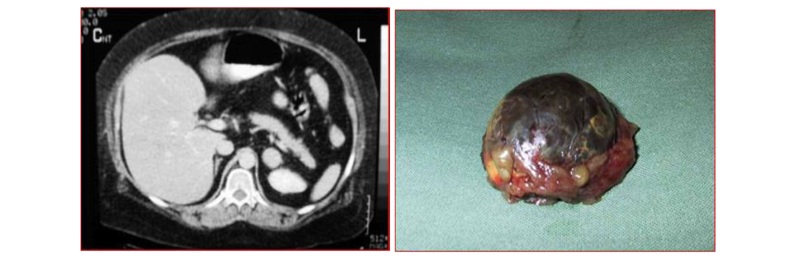

Nefrectomía radical en casos complejos

En relación al tamaño del tumor renal para la vía de abordaje, se ha demostrado que masas renales de > de 10 cm de diámetro, se pueden operar por vía laparoscópica. Determinamos que si los tumores son clínicamente localizados, el tamaño no fue un impedimento para la cirugía. Otros grupos presentaron experiencias similares y concluyeron que no hay diferencias en los resultados, tanto quirúrgicos como oncológicos (21,22) (Figura 22).

Esta cirugía puede efectuarse tanto por un acceso transperitoneal como retroperitoneal, dependiendo de las preferencias del cirujano o de las características particulares del paciente o tamaño del tumor. Cuando se realizan por el acceso transperitoneal, debe movilizarse ampliamente el colon derecho o izquierdo (incluyendo ángulos hepáticos y esplénicos), según corresponda, para extirpar en bloque la bolsa de Gerota y su contenido (Figura 19). En el lado derecho hay que hacer necesariamente una maniobra de Kocher (movilizar el duodeno) para acceder con comodidad al hilio renal (Figura 20).

Una manera segura y sencilla de acceder al hilio renal es disecar la Gerota en su extremo caudal, separándola de su íntima unión con el músculo psoas lumbar. Una vez ubicado el hilio, este debe ser disecado para controlar por separado arteria y vena. Usamos Hem-o-LockTM de rutina, dos proximales y uno distal (Figura 21).

Se seccionan los vasos con tijera fría. En este punto se debe decidir preservar o no la glándula suprarrenal correspondiente o completar la disección del polo superior incluyendo la glándula en la bolsa de Gerota. En el lado izquierdo para preservar la glándula, se debe seccionar la vena renal entre la afluencia de la vena suprarrenal izquierda hacia la vena renal principal y el riñón, ubicar la cápsula renal y abandonar la glándula con la grasa que la rodea. En el lado derecho, posterior a ligar el hilio se debe ubicar la cápsula renal del polo superior dejando la glándula con la porción de grasa del polo superior que la rodea. Se completa la disección de la Gerota en forma roma. Por último se secciona el uréter y los vasos gonadales(19,20).

Una vez liberada la pieza, se atrapa en una bolsa de PVC de 15 cm de diámetro y se extirpa por el sitio de Nyhus, previamente preparado (antes del pneumoperitoneo), marcando el sitio con un lápiz indeleble en la piel y disecando la fosa iliaca cuando la cirugía es retroperitoneal. Recomendamos hacer la marcación de este sitio antes de efectuar el pneumoperitoneo ya que, cambia la disposición anatómica con el abdomen insuflado. La ventaja del abordaje retroperitoneal es que se evita la disección de vísceras intraperitoneales. Como desventaja se tiene un campo quirúrgico más reducido.